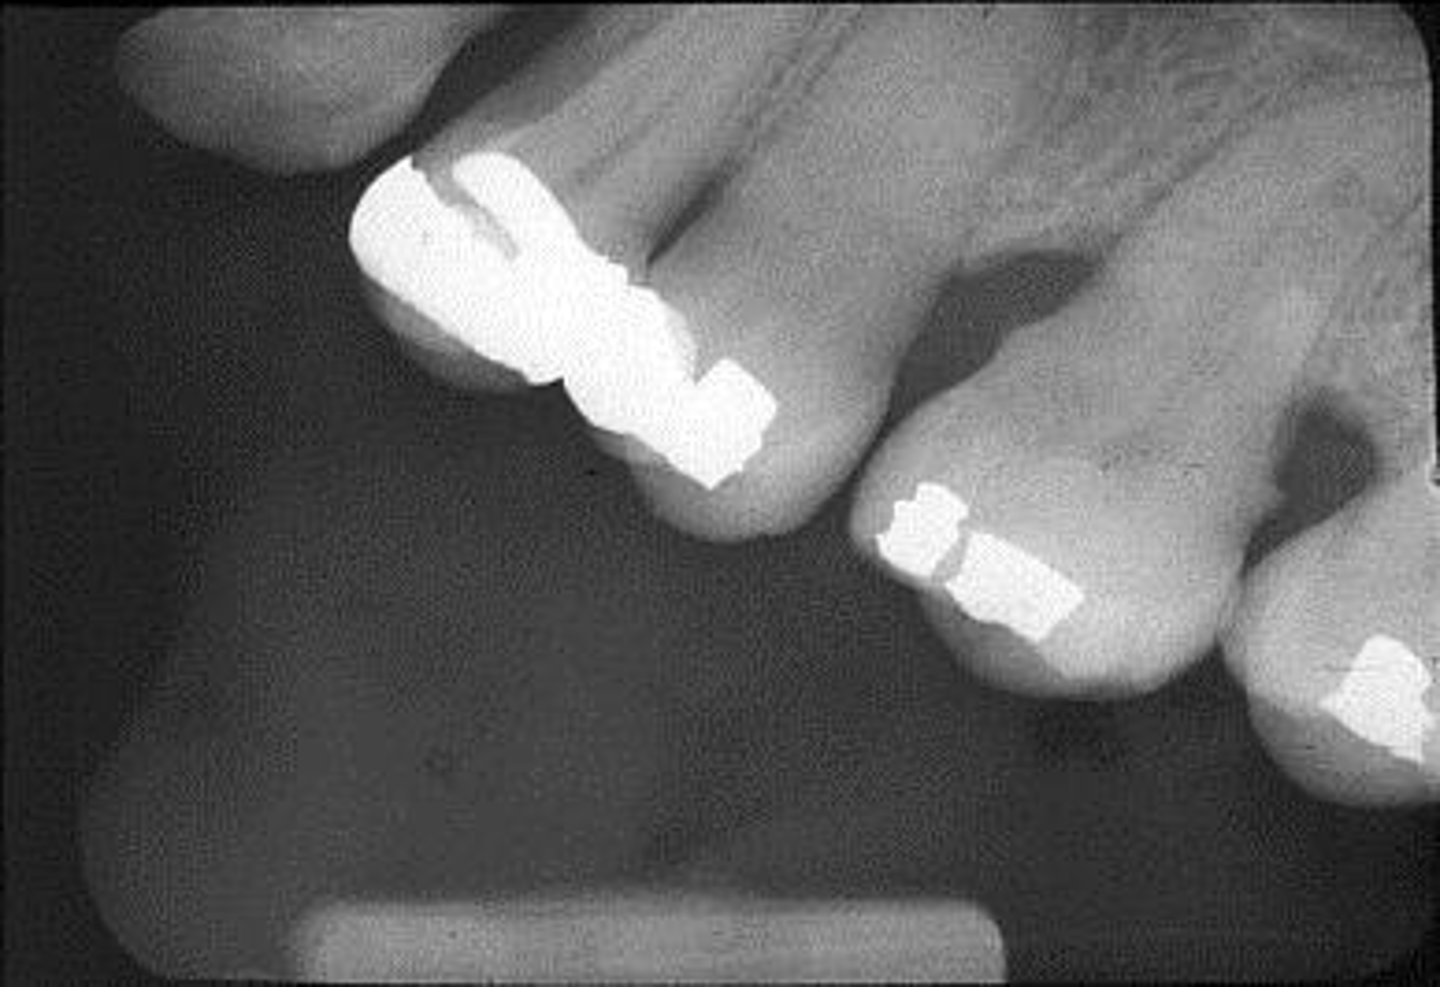

Phalangioma

Appearance-The patient's finger appears on the plate

Cause-The patient's finger was positioned in front of the plate

Correction-Make certain the patient's finger is placed behind the plate (if necessary)